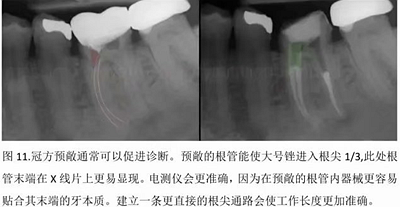

本文的目的是描述一種旨在優(yōu)化根管根尖部分預備的預敞技術。根管頸部或冠方的早期預敞對于減少初尖銼直徑和根尖部根管直徑之間的差異至關重要。大量研究表明,手用或機用器械預敞根管能顯著減少器械折斷的發(fā)生率。